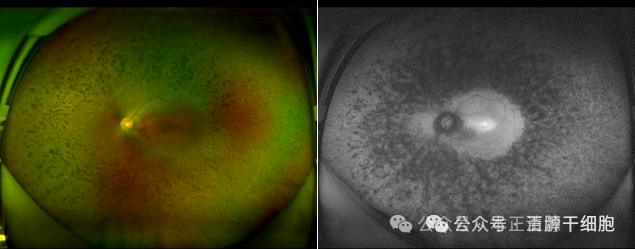

图片

▲图示:视网膜色素变性患者超广角眼底照相及自发荧光